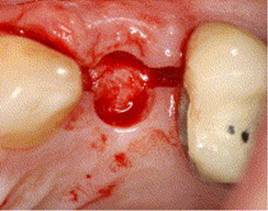

PILOT DRILL